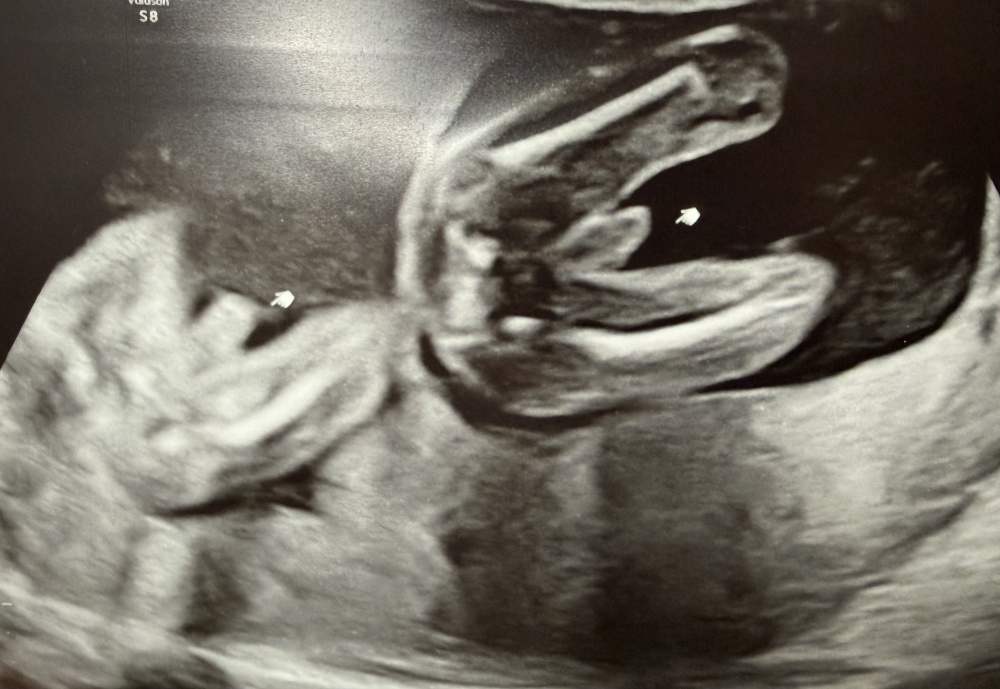

MĂ€dchen oder Junge SSW17

Hallo meine Lieben, waren heute beim Ultraschall SSW17

Das Geschlecht spielt bei uns keine Rolle, da wir bereits einen Jungen und ein MĂ€dchen haben.

Aber aus reiner Neugier, was meint ihr anhand der Bilder, MĂ€dchen oder Junge